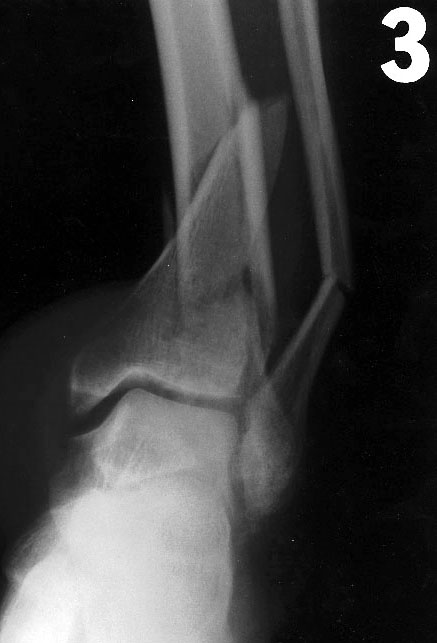

Major pelvic ring disruption, Lateral Compression 2, Tile B2, Lt comminuted pubic ramus fx, Letournel A2, Lt comminuted anterior wall acetabular fx, Lt impacted sacral alar fx, Denis 1, Letournel C, Seattle 2,

11/07/96 Rx Lt anterior wall acetabular fx - 27226 Open rx with fixation of anterior wall, Open reduction, internal fixation, 4.0 mm cancellous screws, 10 hole 3.5 recon plate (enter)